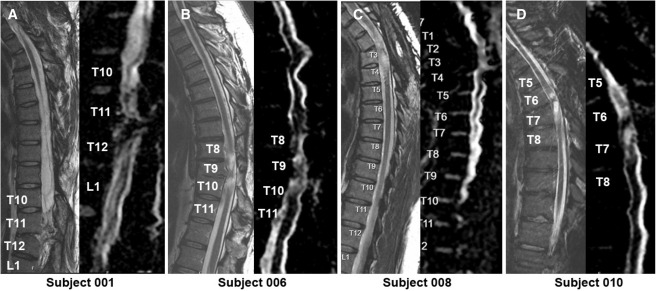

本次發布的I期臨床研究旨在評估神經干細胞移植治療慢性胸椎脊髓損傷的安全性和初步療效。研究選取了四名完全性ASIA-A級胸部SCI患者作為受試者,這些患者的損傷時間均超過一年,且在接受任何其他形式的有效治療后仍未見明顯好轉。

每位受試者接受了每個注射點含有2×105個神經干細胞,通過定制的立體定向設備,雙側注入損傷部位周圍的剩余組織及下方約一個節段的內側白質區,整個過程由術中熒光透視成像指導完成。

臨床結果:

1.神經系統反應概覽:按ISNCSCI隨訪,2名受試者(001、010)在移植后出現了明顯的神經學改善:001在移植后2年曾上升兩個節段,5年回落至上升1個節段;010則在整個5年隨訪期間保持了穩定的神經功能提升。

3.疼痛與生活質量:疼痛方面,001和006報告總體疼痛下降,008疼痛加重且因骶骨潰瘍在30個月時發生嚴重不良事件導致生活自理能力(SCIM)明顯下降,010的疼痛和SCIM變化較小,總體3名患者SCIM未見顯著改善。

4.影像學評估:術后MRI顯示所有患者存在不同程度的局灶性脊髓軟化,但未見新的并發影像學征象(如水腫、增強或積液);DTI提示脊髓束外觀穩定,未見廣泛重塑或纖維束改善。